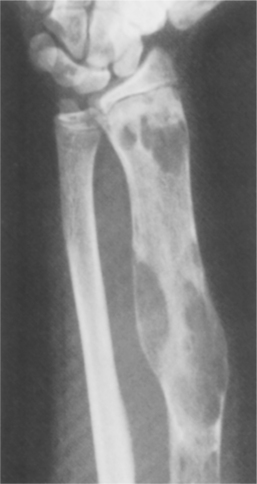

On radiograph the tumor often shows an expansile lesion in the diaphysis of long bones with cortical thickening and destruction of the medullary bone (Fig. 26-13). The appearance is somewhat variable depending on the rate of growth and the host bone response. Biopsy is important not only for accurate diagnosis but also for guiding treatment. Chondrosarcoma can develop on the surface of bone or present as multicentric, involving several bones.

Figure 26-13 Characteristic radiographic features of chondrosarcoma include thickening of the cortex (closed arrow); destruction of the medullary and cortical bone (curved arrows); and soft tissue mass (open arrows). Note the characteristic punctate calcifications in the proximal part of the tumor. (From Greenspan A: Tumors of cartilage origin, Orthop Clin 20:359, 1989.)